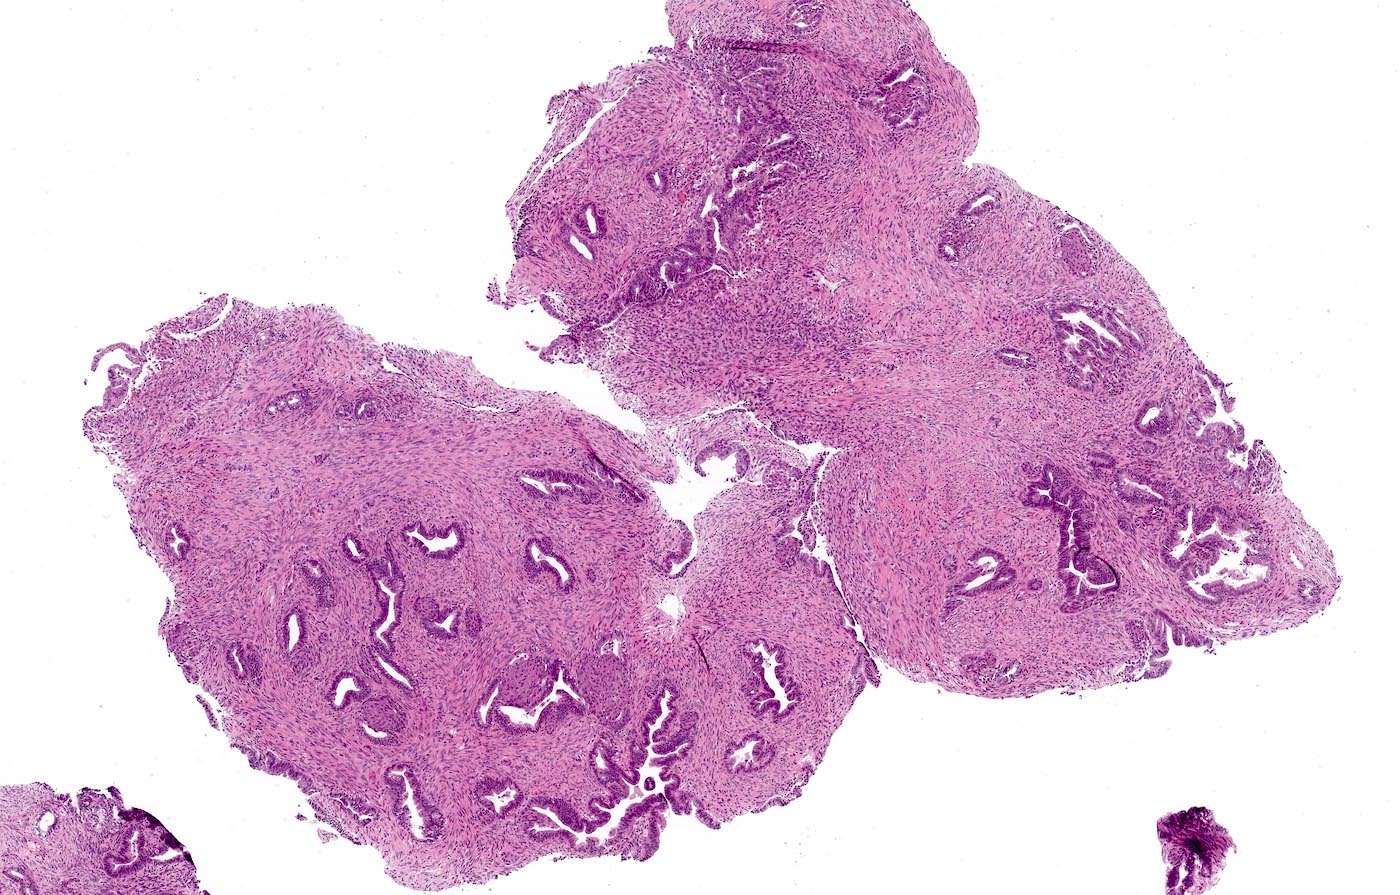

Microscopic (histologic) description

- Biphasic tumor:

- Endometrioid glands, usually with complex architecture and sometimes with cytologic atypia

- Glandular component often shows lobulated architecture

- Benign fibromyomatous stroma, rarely with myxoid change

- Squamous morular metaplasia is frequently seen and may show central necrosis

- Well circumscribed or slightly irregular margin

- Reference: Am J Surg Pathol 2015;39:1148

Microscopic (histologic) images